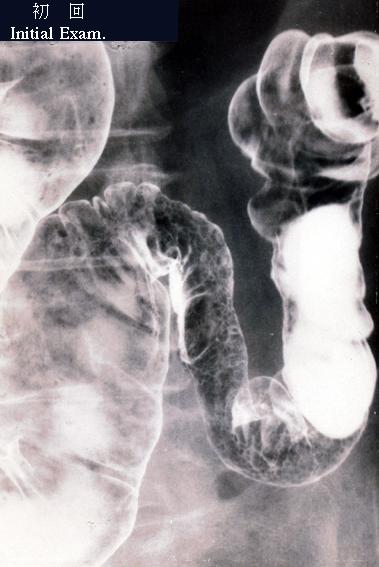

虚血性大腸炎のX線像  横行結腸の中央部から脾弯曲部にかけて、腸管の狭小化がみられます。そして口側には、縦走する潰瘍が認められます。

疾患(病理主体)の分類炎症性・潰瘍性疾患/虚血性腸炎

部位(臓器別)大腸/横行

検査方法X-P